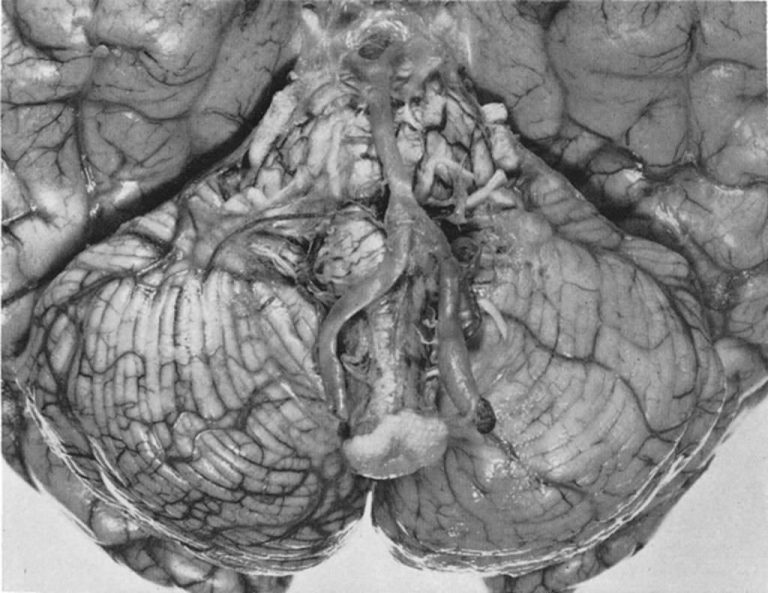

المخيخ هو جزء من الدماغ يتحكم في الحركة ويحافظ على التوازن. إنه موجود في الجزء الخلفي من عقلك، في الجزء السفلي. لديه الجانب الأيسر والأيمن متماثل. يتحكم كل جانب في التنسيق والحركة في الجانب المقابل لجسمك.

هناك عدد من الأوعية الدموية التي تغذي المخيخ. الجلطة الدموية في أي من هذه الأوعية يمكن أن تسبب سكتة دماغية. تشمل الأوعية التي تصل إلى هذا الجزء من الدماغ: